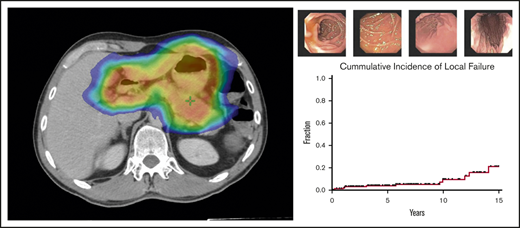

Treatment response to radiotherapy was assessed at 3 months by follow-up EGDs with multiple biopsies (Figure 2). Among the 166 patients who were treated for early-stage GML, posttreatment EGD with biopsy was performed in 160 patients, of whom 152 (95%) demonstrated a complete pathologic response (Wotherspoon 1-2) on the first posttreatment biopsy. Patients were serially followed by EGD biopsies in increasing intervals of 3 to 24 months.

EGD images documenting pathologic complete response. EGD images from patient 6, whose experienced spontaneous normalization without salvage treatment.

Over this extended follow-up period, 15 of 160 patients (9%) were found to have residual disease on EGD posttreatment biopsy (Wotherspoon 5; Figure 3). In addition, atypical lymphoid cells, not diagnostic of lymphoma (Wotherspoon 3-4), were described in 15 of 160 patients (9%). Six of the 15 patients (40%) with residual lymphoid cells subsequently progressed to local failure. Three of 20 patients (15%) with posttreatment residual disease experienced spontaneous resolution of their pathologic abnormalities on subsequent biopsy and, thus, were considered free of disease. The median interval from last radiation treatment to spontaneously resolved biopsy was 9 months (range, 8 months-3 years).

Natural history of EGD abnormalities. Fifteen patients who presented with early-stage GML exhibited residual GML on posttreatment EGD biopsy. Pathology review reported no evidence of disease (green circle), atypical lymphoid cells (blue circle), or residual GML (red open circle). Five patients with atypical lymphoid cells subsequently progressed to local failure (patients 2, 3, 4, 5, and 9). Three patients (6, 8, and 14) had pathologic EGD failures that self-resolved with observation alone.

Over a median follow-up of 6.2 years from the end of RT (range, 19.7 months-23 years), 12 of 166 patients (7%) treated for early-stage disease experienced local failures. Five-year and 10-year local failure rates, using death as a competing risk, were 3.9% and 8.3%, respectively (Figure 4). Median time to local disease failure was 4.4 years (range, 3 months-14 years). One patient who developed DLBCL of the stomach 1 year after RT was treated with cyclophosphamide, doxorubicin, vincristine, and prednisone (CHOP) chemotherapy and died of disease a year later. The remaining local relapses were associated with refractory GML on EGD biopsy. Salvage therapies included rituximab, additional radiotherapy, and rituximab (R)-CHOP.

Local and distant disease failures. Cumulative incidence of local and distant failures for patients treated for early-stage GML (N = 166), using death as a competing risk. Five-year and 10-year local failure rates were 3.9% and 8.3%, respectively, whereas 5-year and 10-year distant failure rates were 6.9% and 11%, respectively.

Among patients treated for early-stage disease, 16 of 166 patients (10%) developed distant sites of disease. Five-year and 10-year distant failure rates were 6.9% and 11%, respectively (Figure 4). Median time to distant disease failure was 4.7 years (range, 11 months-15 years). Four of these 16 patients (25%) presented with transformation to DLBCL at distant sites, including colon and retroperitoneum (2 patients each). Median time to DLBCL transformation was 3.6 years (range, 11 months-4.7 years). Despite distant relapse, all 16 patients were found to be free of local disease on posttreatment EGD biopsy. Subsequent treatments included chemotherapy, additional radiation, rituximab monotherapy, salvage surgery, and observation.